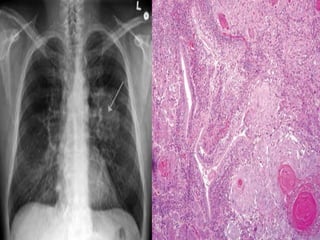

SQUAMOUS CELL CARCINOMA

 Central .

 25-30% of lung cancer .

 Arise from bronchial epithelium. Hilar mass

arising from bronchus.

 Cavitation may also occur.

 Slow growth, metastasis not common.

 Can cause Hypercalcemia (produces PTHrP).

 Histology: Keratin pearls D and intercellular

bridges